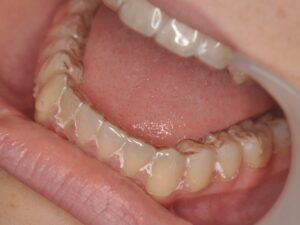

- d’un fil collé sur la face interne (linguale) des dents

- de gouttières passives de stabilisation réalisées sur mesure. `